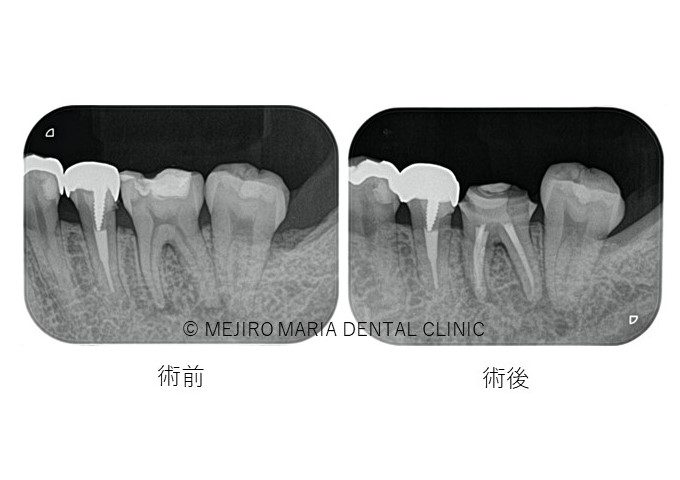

治療終了後、良好に根の中にバイオセラミックが充填され封鎖できていることを確認し(画像A)、3ヶ月後の経過観察にて、痛みや違和感がないことはもちろんのこと、術前、術後に確認できていた根尖性歯周炎の透過像の縮小を確認(画像B)し経過が良好であると判断しました。

目白マリア歯科【症例】初回根管治療(歯髄壊死)|患者様利益を考えた精密根管治療_治療後_術前術後の比較レントゲン画像

この患者様はお仕事の都合上、多くの回数を歯科医院に来院されることが難しい患者様でした。今回の治療も2回の来院で根管治療を終了し、3ヶ月後に経過観察を行い問題がないことを確認し治療を終了いたしました。合計で4回の来院で治療を完了しました。

精密根管治療のメリットの一つは少ない回数で治療が完了し、予知性が高い処置を行うことができることです。

なお、今回は初めての根管治療である抜髄(歯の神経を取る治療)を精密根管治療で実施いたしました。コンセプトに沿った無菌的な処置を初回の根管治療で行うことで、根管治療による細菌増殖リスクや何度も根管治療を繰り返すことで歯質が少なくなることによる抜歯リスクも回避することにつながり、患者様にとって有益な治療であることもお伝えしたいと思います。